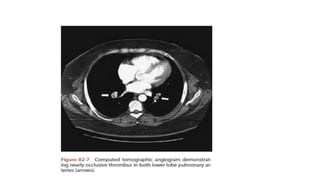

Role of CT Pulmonary Angiogram- MDCT with

contrast

• At the present time, CT is considered confirmatory in excluding

embolism in patients with a low or intermediate likelihood of disease

and confirming embolism in patients with intermediate or high

probability of disease.

• When discordance exists between the clinical assessment and CT

findings, additional studies should be performed.

• It is possible this recommendation will change as studies with 64-

MDCT scanners are published.

Pulmonary Angiogram- Gold Standard

• Pulmonary angiography remains the accepted “gold standard” for PE

diagnosis.

• Only two angiographic findings are diagnostic of acute embolism: the

filling defect and abrupt cutoff of a vessel.

• Catheter is inserted in the right heart and dye is injected into

pulmonary trunk. Filling is observed under fluoroscopy.

• Limitations of Pulmonary Angiogram

• It requires expertise in study performance and interpretation;

• it is invasive.

• High mortality due to procedure itself.

Pulmonary angiogram showing multiple emboli